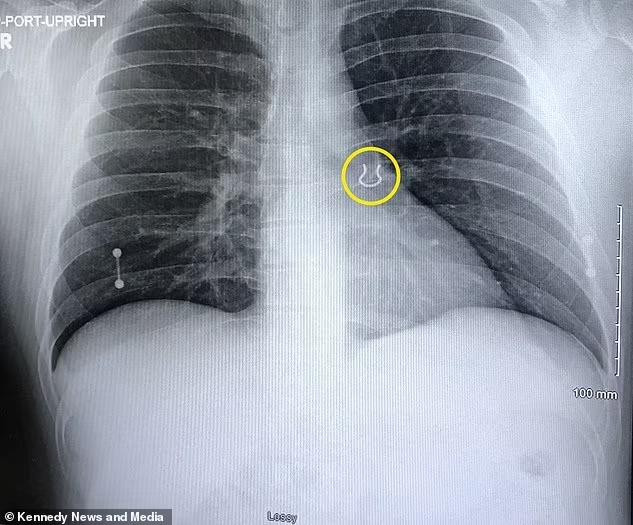

Ban đầu, các bác sĩ lo ngại bệnh nhân bị bệnh viêm phổi. Tuy nhiên, kết quả chụp X-quang cho thấy có dị vật nằm bên trong thùy trên phổi trái của Lykins. Đó là mảnh kim loại có kích thước khoảng 1,5 cm.

| Chiếc khuyên mũi mắc kẹt trong phổi suốt 5 năm. Ảnh: Daily Mail. |